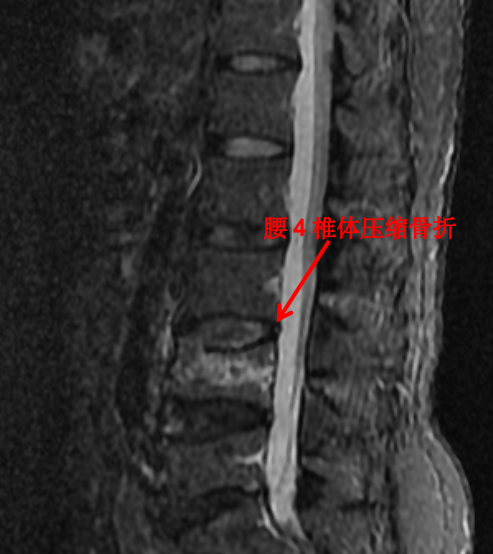

随着科技进步及医学的发展,核磁已经是脊柱外科不可或缺的检查手段。对脊柱、韧带、椎间盘、椎管内神经及椎旁组织显影都优于 CT,通过腰椎核磁我们可以直观地看到椎间盘突出的程度、神经受压的程度,以及压缩骨折的新鲜程度。

前面提到的腰椎压缩骨折,X 光片可以看出楔形变,但无法判断新鲜骨折还是陈旧骨折,进一步完善腰椎 MRI 才能明确诊断,做出下一步治疗计划。